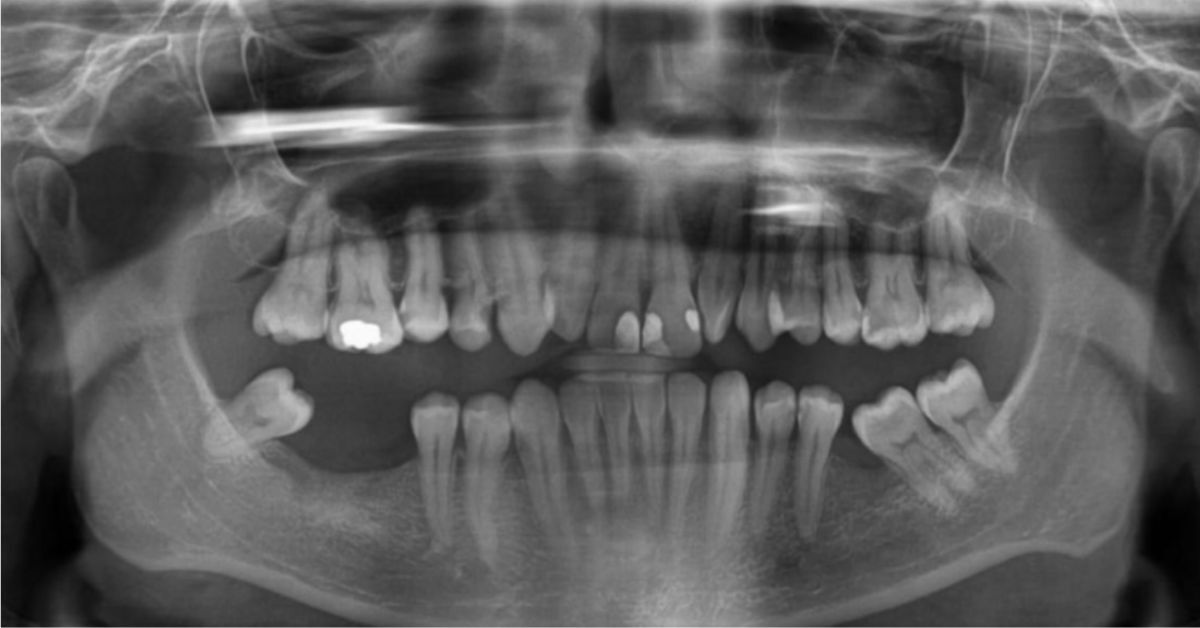

Unlike traditional 2D X-rays, which give a flat image, a 3D CBCT scan shows the full picture – allowing your surgeon to see every angle and every millimetre of bone before planning your implant placement.

Initial Consultation: your dentist performs an oral examination and reviews your 2D X-ray to get a general overview.

A traditional X-ray can offer a general idea, but it cannot show the true depth, density, or 3D shape of your jawbone. Only a CBCT scan can give a 100% clear picture – allowing your surgeon to make objective decisions about: